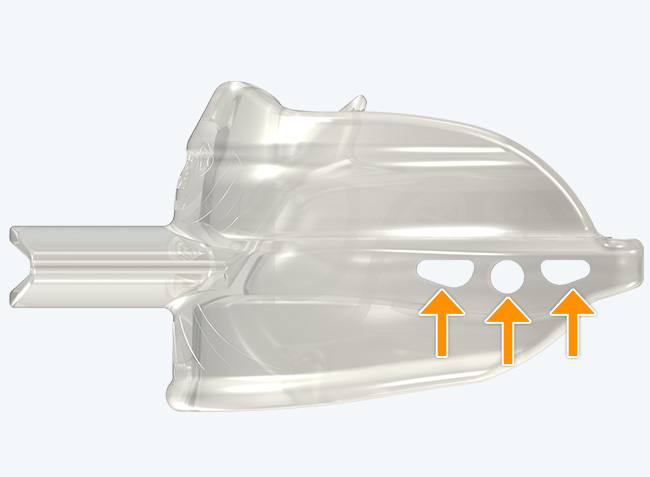

The Myosa® for TMJBDS® S1H is specifically designed for patients who are breathing and disordered sleep (BDS) primary with moderate to severe BDS as indicated by a Breath Hold Time (BHT) of 20 or less. These patients may or may not have TMJ disorders, but due to the severity of their BDS, they require immediate improvement of their airway. The features of the appliance not only work to open the airway, but also allow patients to undertake initial exercising of the lip, tongue and airway muscles. Progress to the S1 when the patient’s BHT reaches 20 seconds or more.